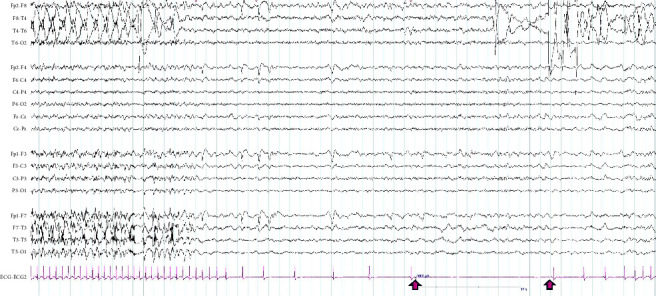

Background: Ictal arrhythmia is a rare condition that causes arrhythmic manifestations induced by epileptic seizures, including asystole or bradycardia. Ictal asystole (IA) is a very rare condition found in patients undergoing video-encephalography (EEG) monitoring. It is often related to temporal lobe epilepsy and can cause syncope, which can lead to injury or even death. Case Presentation. Two patients with epilepsy showed symptoms of syncope. Both patients underwent 4-day ambulatory EEG tests and were diagnosed with IA. Following the tests, the patients were implanted with a permanent pacemaker, and one of them underwent a temporal lobectomy. As a result of these procedures, the patients experienced a reduction in episodes of symptomatic syncope.

Conclusion: Patients with ictal asystole and symptomatic ictal bradycardia are at increased risk of falls due to seizures. Although there are no specific guidelines for managing this condition, antiseizure medications, epilepsy surgery, and cardiac pacemaker implantation have been effective treatments.